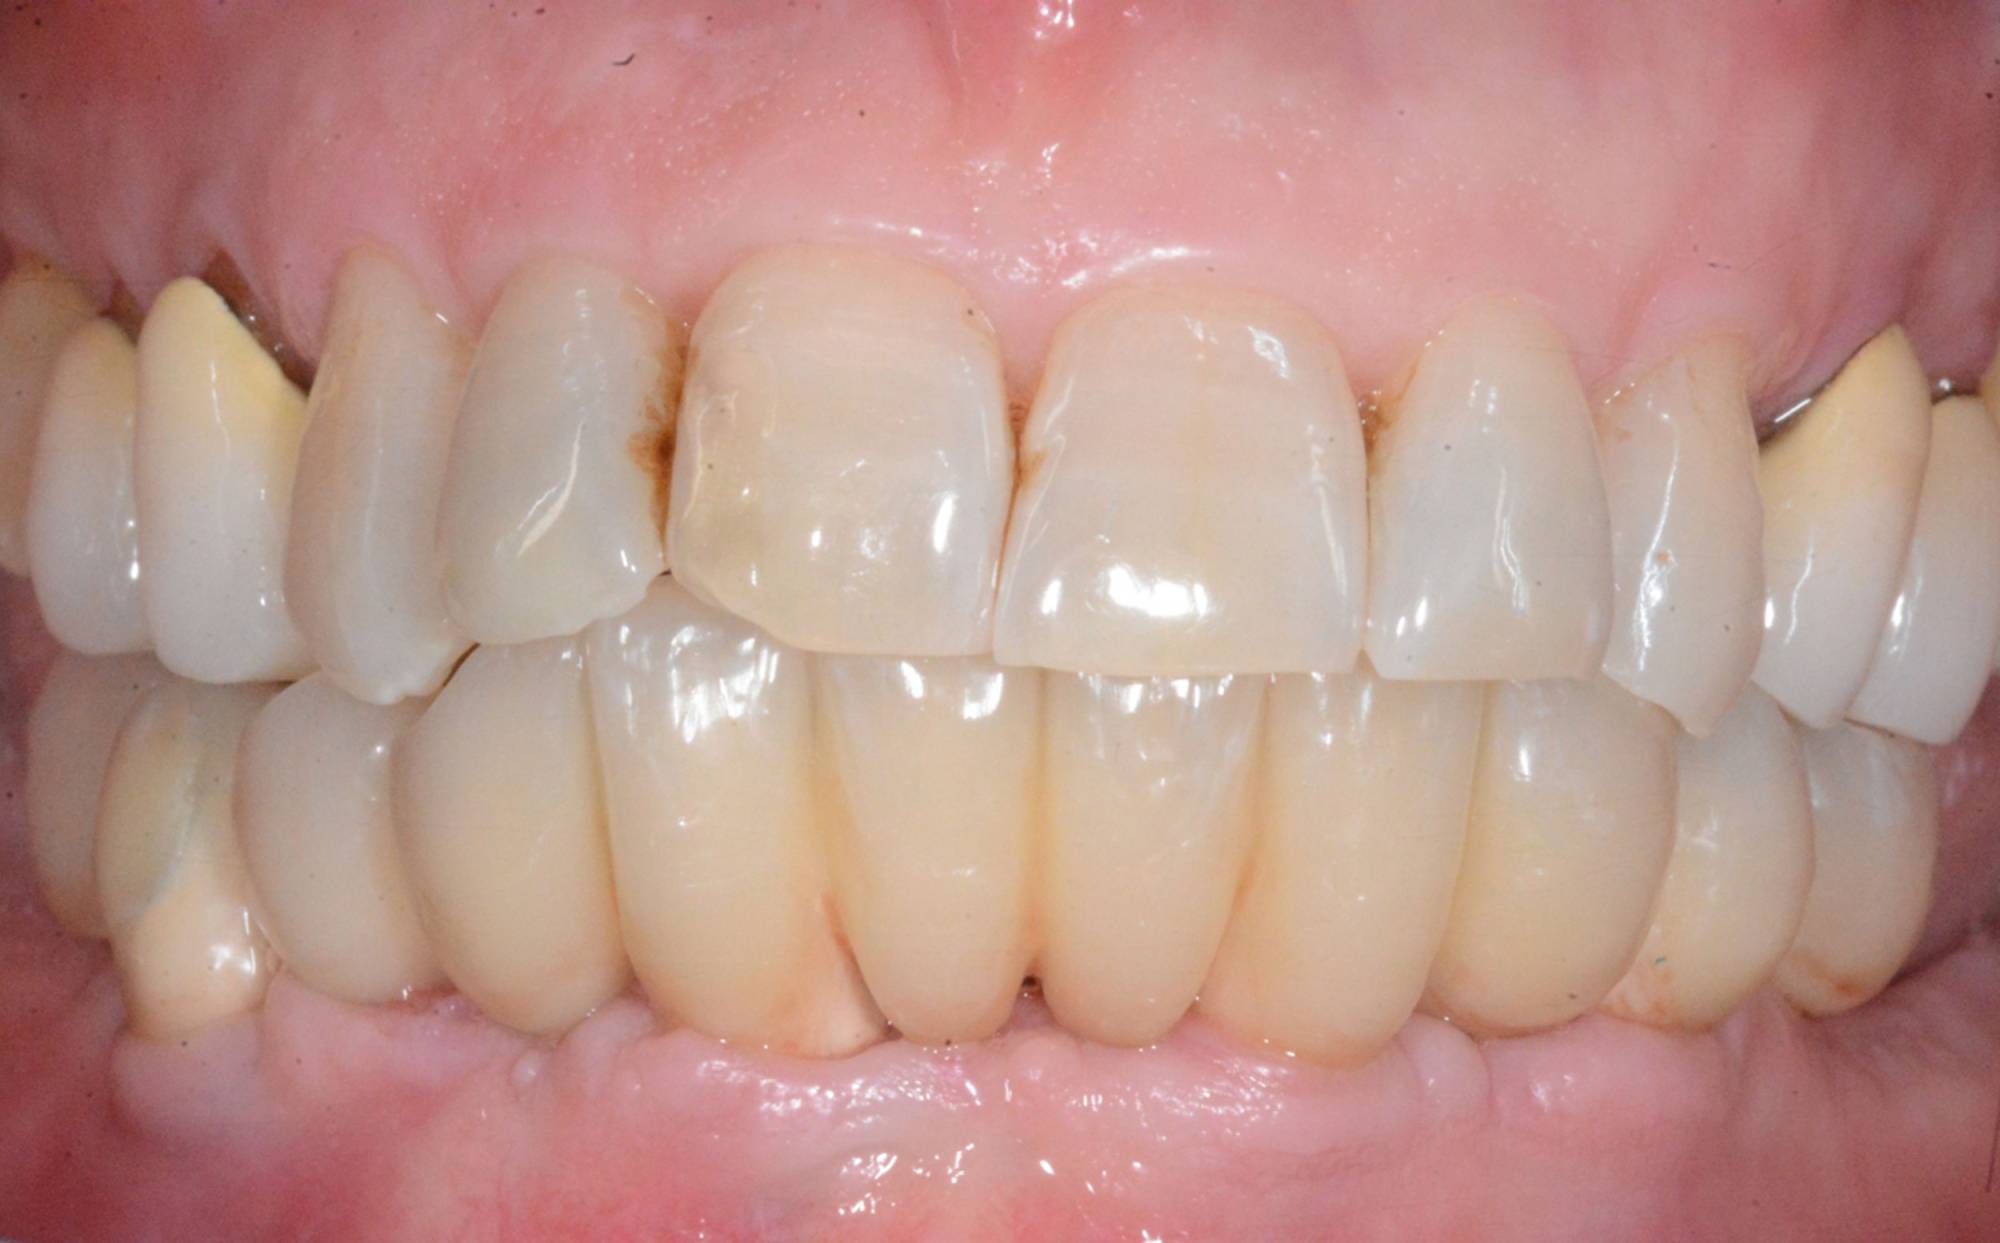

L'impianto, oltre a essere un metodo sicuro, garantisce l'aspetto esteriore e la piena funzionalità di un dente naturale. Oltre a ciò, mantiene l’integrità dell’osso, non va ad intaccare i denti adiacenti - come invece farebbe un ponte - e migliora l’estetica facciale prevenendo la perdita ossea.

Gli impianti sono molto versatili e possono essere usati per sostituire un dente singolo, più denti fissi o addirittura un'intera arcata. Inoltre, possono essere inseriti sotto una protesi mobile per stabilizzarla migliorandone il comfort.